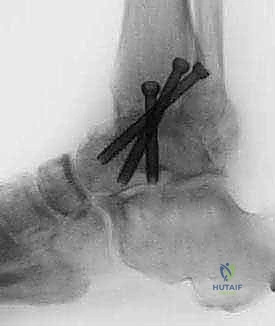

TECH FIG 3 • (continued) D. Three cannulated screws are inserted over the guide pins for definitive fixation of the arthrodesis.

TECH FIG 3 • (continued) E. Final AP and lateral radiographs confirm appropriate screw placement and position of the arthrodesis.

FIG 2 • AP and lateral postoperative radiographs are evaluated to ensure the desired alignment of the arthrodesis and check the screw position.